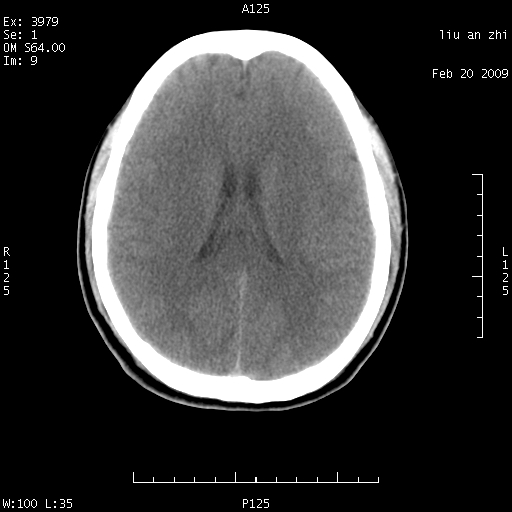

患者:男,32岁 被打伤后3天,自感头昏头痛作头颅ct检查。请大家看一下想什么??

请注意小脑幕!!!

ct18448的结果:mri检查左侧天幕下血肿